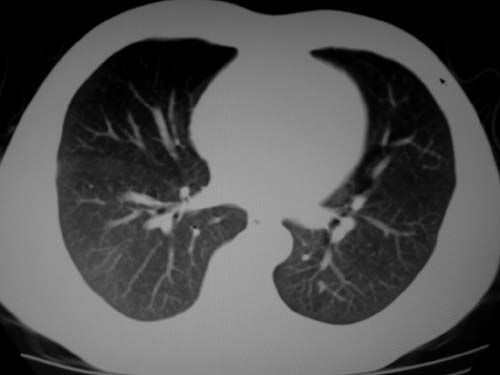

标题: CT19540: 31岁。自述结核性胸水治疗两个月后,在外院拍x线发 [打印本页]

标题: CT19540: 31岁。自述结核性胸水治疗两个月后,在外院拍x线发

右侧胸壁结节状软组织影伴相应肺叶内受侵,伴右侧胸腔积液。考虑:结核性可能大。

1、炎性病变,结核可能;2、右侧少量胸膜积液。

右侧胸壁结节状软组织影伴相应肺叶内受侵,伴右侧胸腔积液,结合临床,首先考虑结核。

1)考虑右侧结核性胸膜结节。2)右侧胸膜增厚+包裹性胸腔积液。

结核性脓胸、肺内结核?